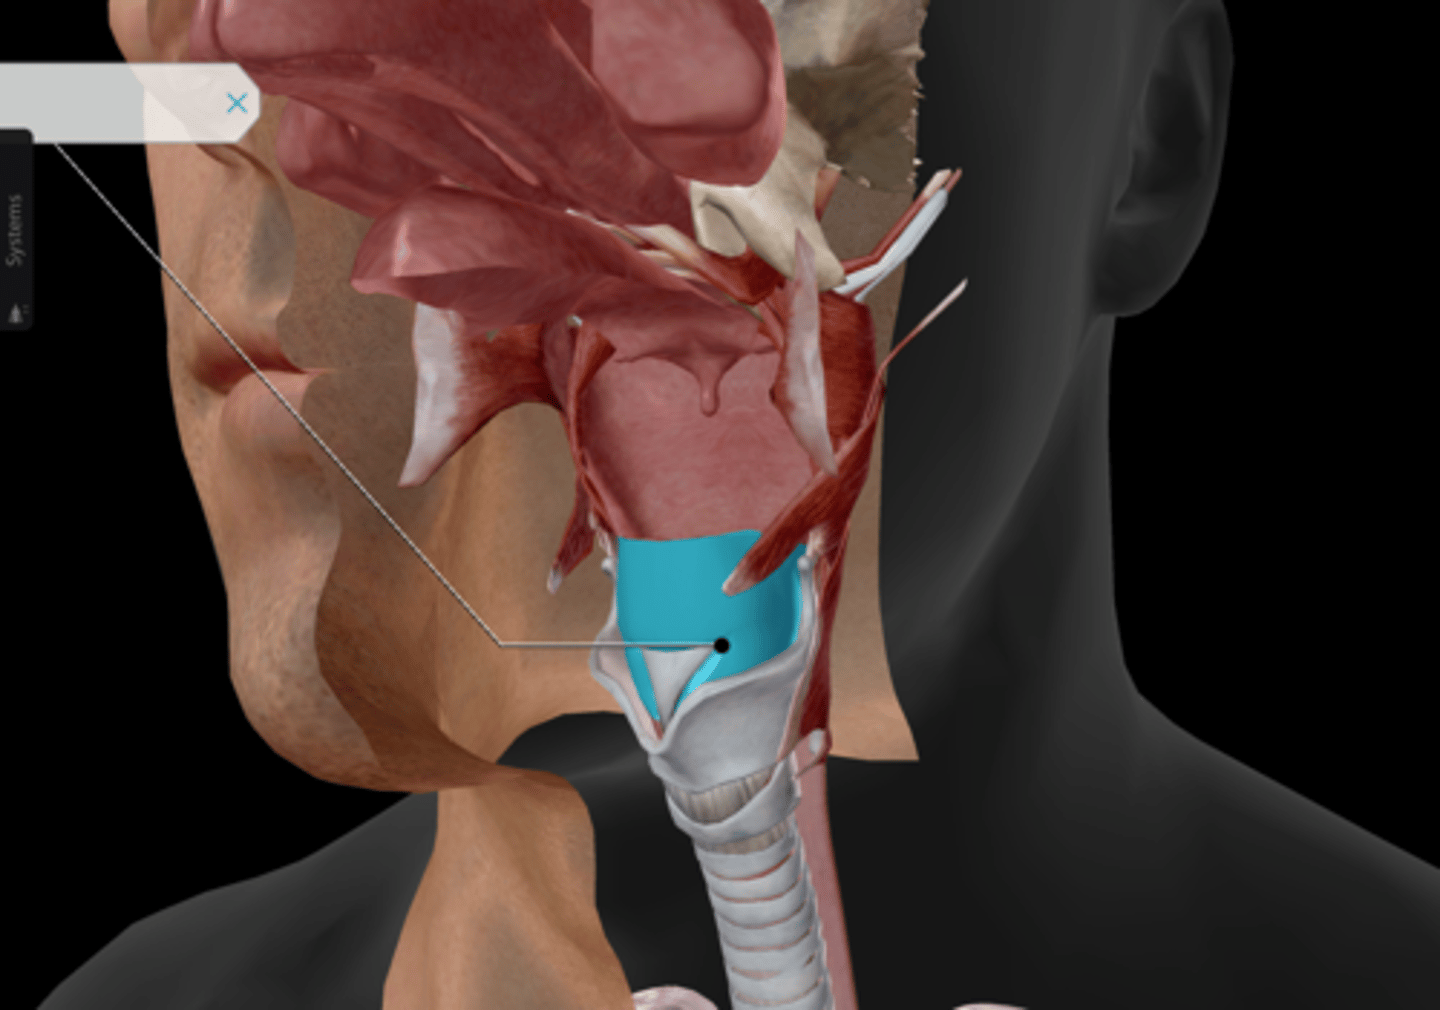

Laryngopharynx

Larynx

Epiglottis

Thyroid cartilage

Cricoid cartilage